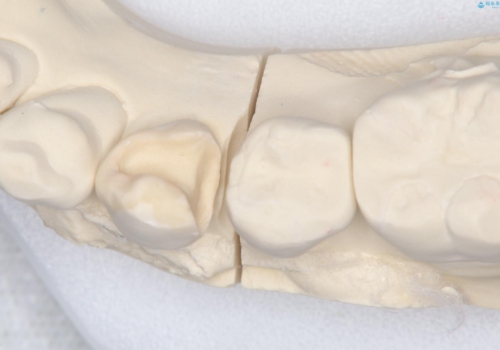

- 主訴:下の歯に入っている銀歯が笑うと目立つので白くしたい。

下顎臼歯部に入っている保険適用のメタルインレー(4箇所)を、審美性・適合性・清掃性の良いセラミックインレーにてやり替えました。